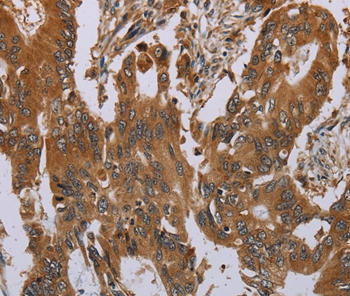

Immunohistochemical analysis of paraffin-embedded Human cervical cancer tissue using #37783 at dilution 1/40.

Immunohistochemical analysis of paraffin-embedded Human colon cancer tissue using #37783 at dilution 1/40.